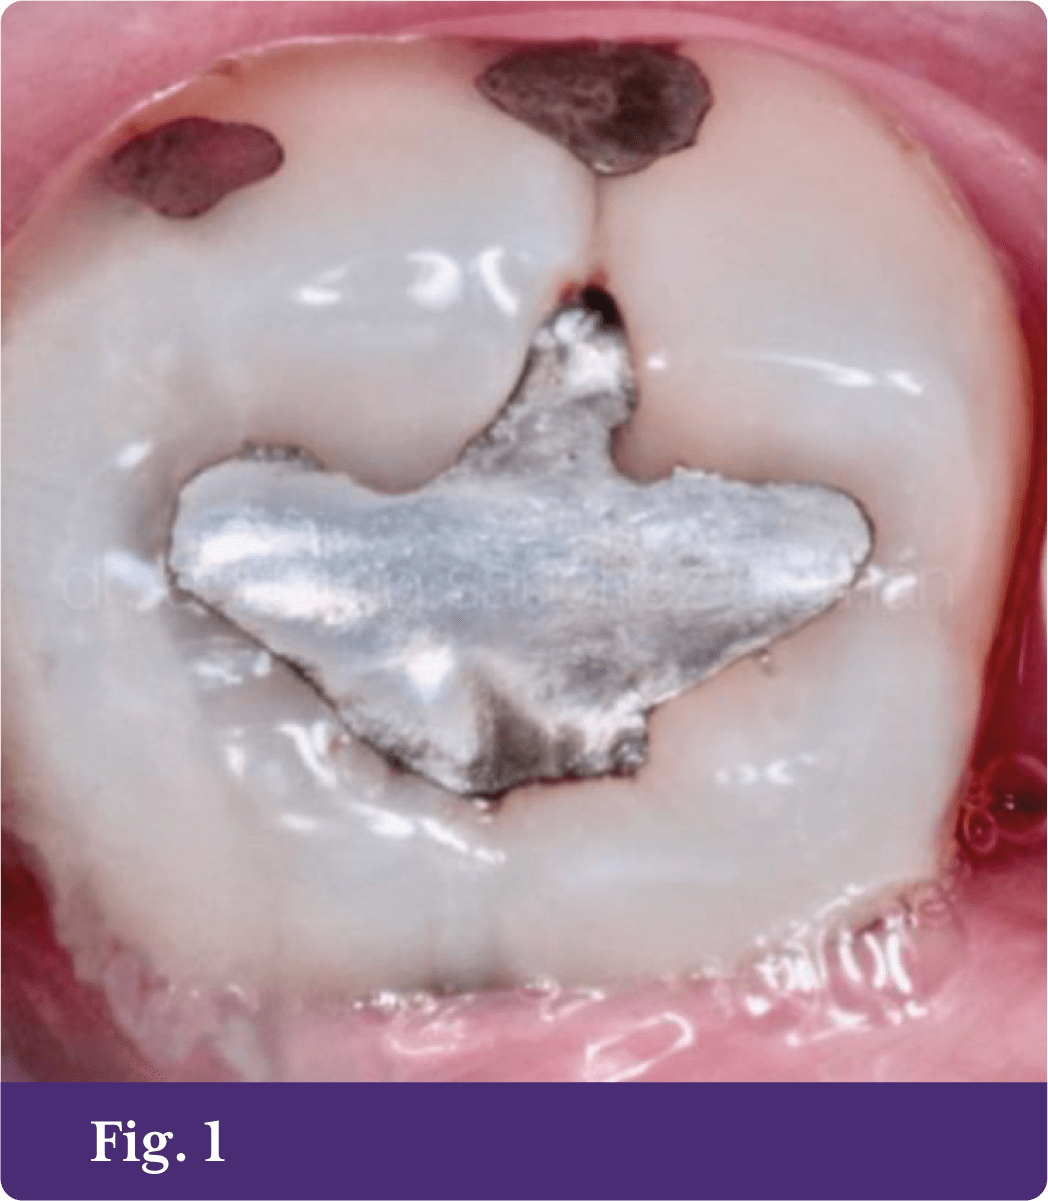

En el piso de la cavidad oclusal se observa dentina reaccional en tono marrón oscuro; en general, las cavidades se ven con buen soporte estructural y prácticamente no se modifican. Se realiza alisado de paredes, desinfección con clorhexidina durante 15 segundos, se acondiciona el tejido adamantino con ácido ortofosfórico al 34% durante 15 segundos, después se lava y retira el exceso de humedad, también se utilizó adhesivo Self etch de dos pasos, dos frascos (primer y bond) de acuerdo a las indicaciones del fabricante y se procede a las obturaciones de las cavidades con composite Aura SDI (fig. 3)3,4 siguiendo las instrucciones. Finalmente, la técnica de obturación fue estratificación oblicua,5, 6 los estratos de dentina fueron hechos con composite color D3,6 (fig. 4).

Los estratos de superficie se realizaron con composite color E1. La versatilidad de la resina Aura SDI permitió lograr resultados muy naturales6 y un sellado marginal imperceptible a simple vista. Se colocó Stain Dark Brown para un efecto de profundidad (fig. 5).